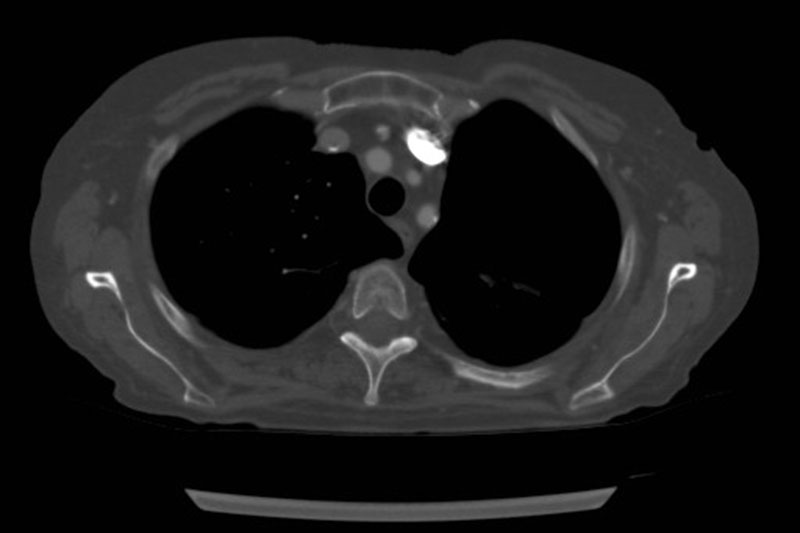

Window/Level

optimized for bones

All viewers support this!